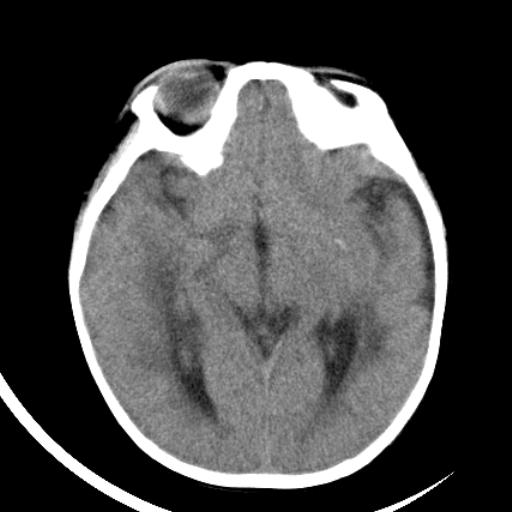

双侧脑室前后角周围白质片状低密度影,双侧侧脑室旁、双顶叶皮层及皮层下多个小原点状钙化灶,不除外torch感染。右顶叶脑回似乎较对侧大,建议mri检查以除外脑发育异常。

考虑:1、巨脑回畸形(皮质明显增厚+脑回明显增宽+白质减少)。

2、torch综合征(室管膜下钙化+白质内及皮髓质交界处多发钙化)。

结节性硬化并无脑回畸形,左侧枕顶叶不排除血管畸形。